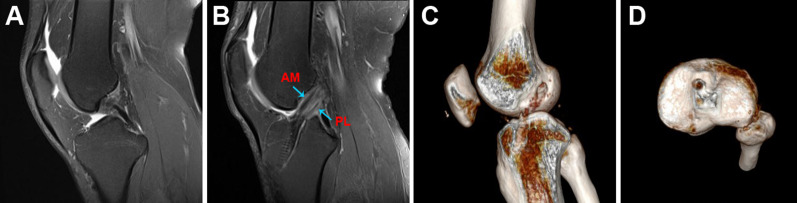

Postoperative 3D CT showed accurate bone tunnels and properly positioned screws in both groups, and the low signal intensity of the ACL graft in the T2-weighted MRI at the last follow-up suggested graft maturation in both groups (Figs. 5, 6). No radiograph indicated joint space narrowing or degenerative change at the last follow-up.

Fig. 5.

Radiological examination of STSB ACL reconstruction. A Preoperative MRI showed ACL rupture. B MRI at the last follow-up showed complete graft healing. C 3D CT showed the femoral socket and the tibial tunnel. D 3D CT showed the tibial socket

Fig. 6.

Radiological examination of STDB ACL reconstruction. A Preoperative MRI showed ACL rupture. B MRI at the last follow-up showed complete graft healing. C 3D CT showed the femoral socket and the tibial tunnel. D 3D CT showed the tibial socket